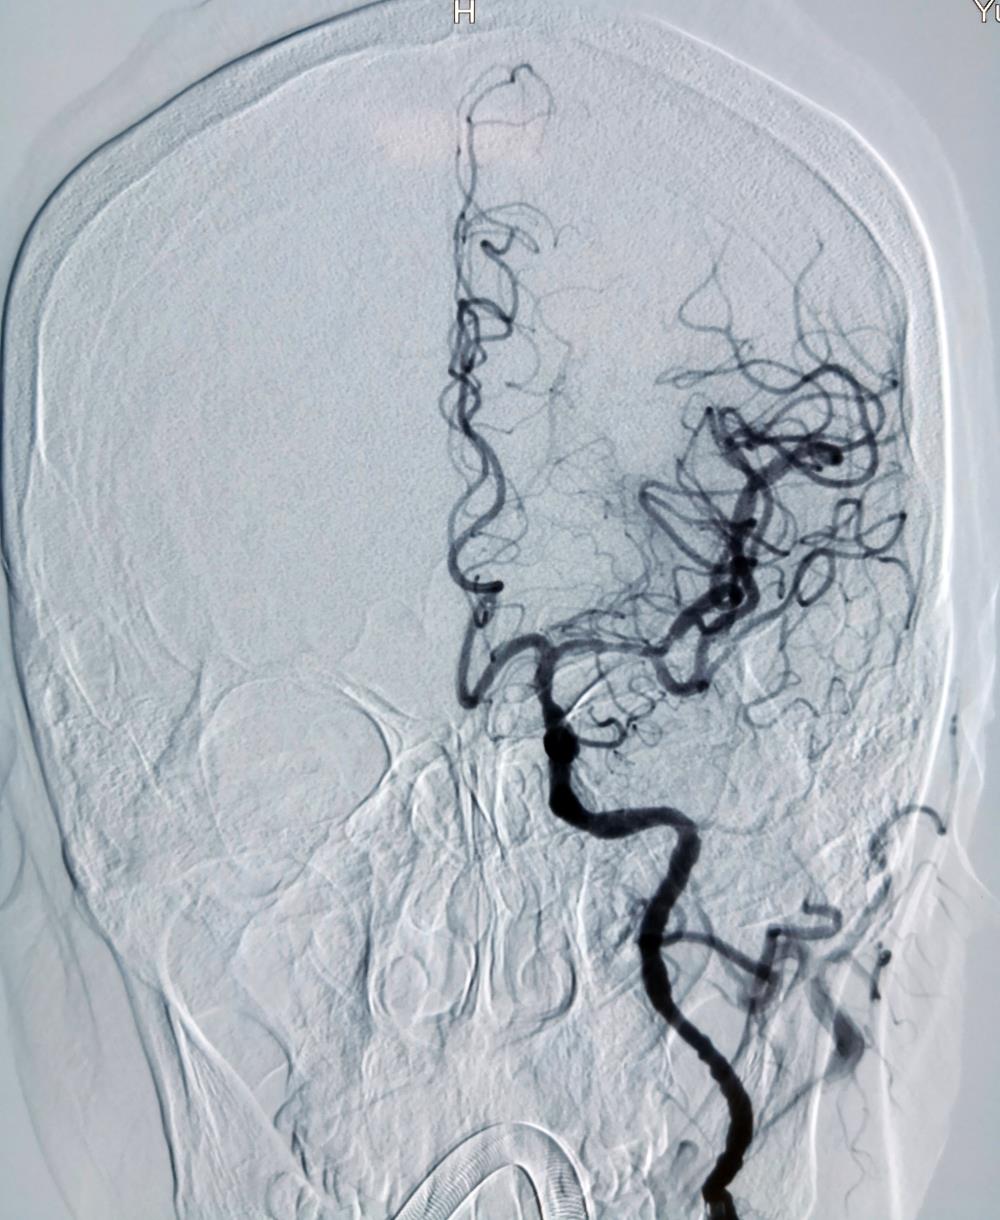

DSA提示左侧大脑中动脉M1段闭塞

DSA提示左侧大脑中动脉完全再通

术后头颅MRA提示左侧大脑中动脉显影良好

经过紧张救治,纪文军博士团队成功在40分钟之内顺利取出血栓,打通血管梗塞部位,挽救了患者的生命和神经功能。因抢救及时,术后胡某恢复良好,神志清醒,肢体肌力已基本恢复正常,宣告了本次手术圆满成功。